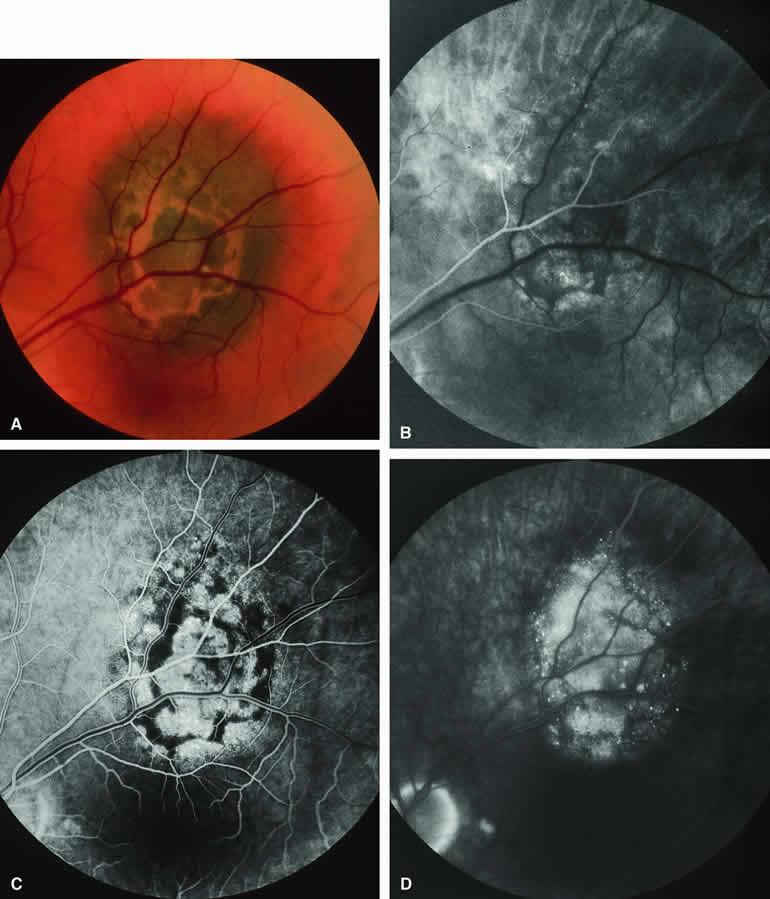

Choroidal Melanoma With Nodular Eruption Through Bruch's Membrane

If a choroidal melanoma has erupted through Bruch's membrane (Figs. 13A and 14A), it forms an apical nodule that is generally hypomelanotic and contains many large-caliber blood vessels. Fluorescein angiography of these tumors (see Fig. 13B, C, and D) typically shows hypofluorescence of the base of the lesion during the early frames, relatively rapid filling of the prominent blood vessels in the apical nodule during the venous and recirculation frames, and intense late staining of the apical nodule resulting from progressive fluorescein leakage by the late-phase frames. Similarly, ICG angiography of these tumors (see Fig. 14B, C, and D) also shows relative early hypofluorescence of the tumor base, early filling of prominent intralesional blood vessels within the apical nodule, intense staining of the apical nodule by the recirculation phase frames, and persistent late hyperfluorescence of the mass.

Fig. 13. Choroidal melanoma with nodular eruption through Bruch's membrane. A. Mushroom-shaped choroidal melanoma inferonasal to optic disc, showing dark basal region and lighter apical eruption through Bruch's membrane. Note prominence of intralesional blood vessels within apical portion of lesion. B-D. Fluorescein angiogram of lesion. B. Arterial phase frame showing fluorescence of large-caliber blood vessels within hypofluorescent apical nodule of tumor. C. Venous phase frame showing increased prominence of intralesional blood vessels, as well as alterations of retinal capillary bed where retina is thinned over apex of tumor. D. Late-phase frame showing intense hyperfluorescence of apical nodule of tumor.